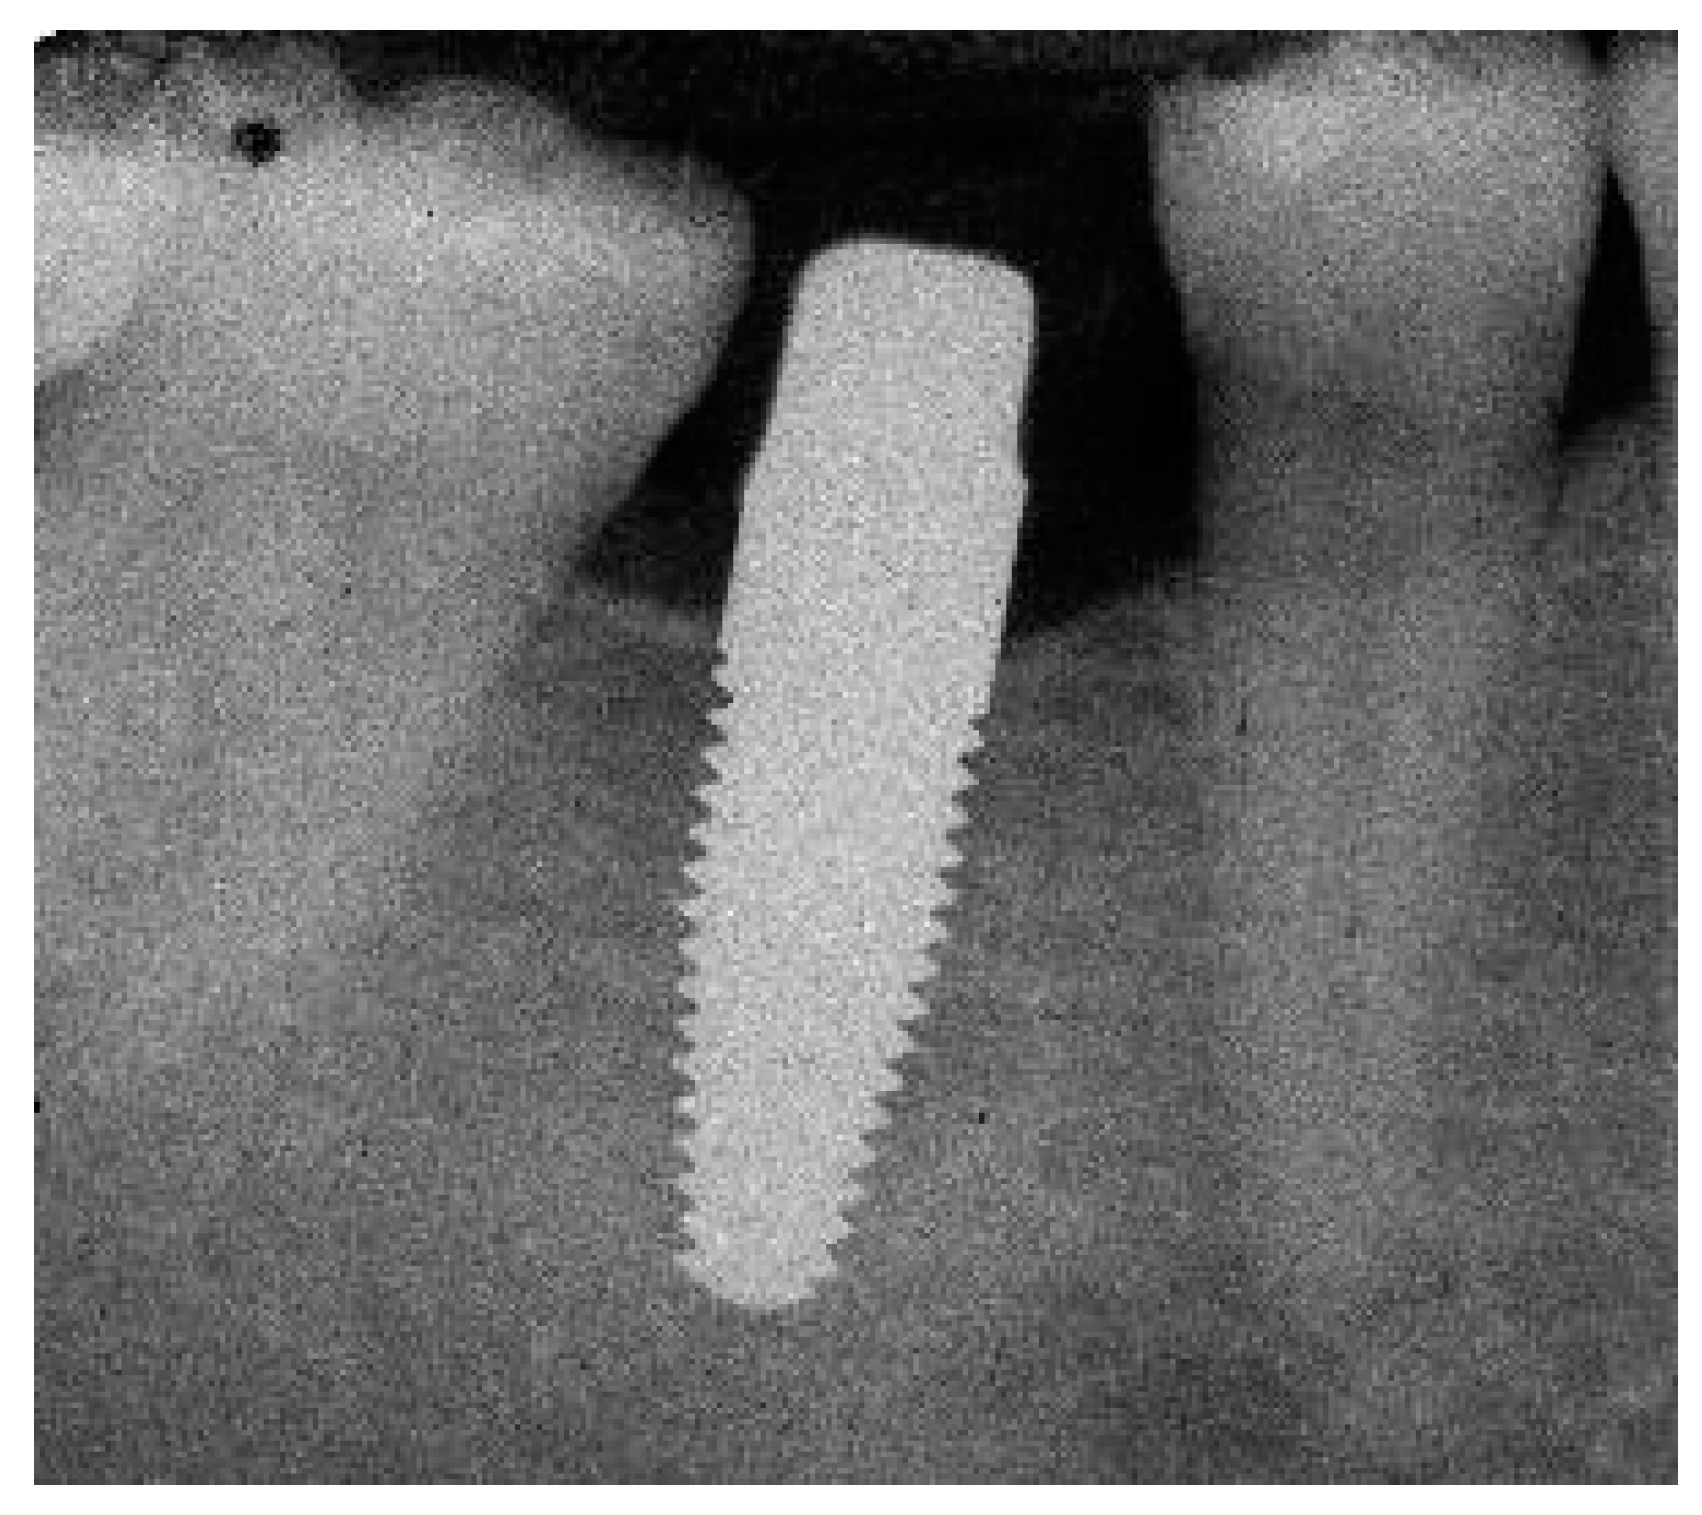

Appendix A. Exemplary Photographs and Radiographs from a Patient at Different Examination Time Points and a Positive Outcome

Appendix B. Exemplary Photographs and Radiographs from a Patient at Different Examination Time Points and a More Negative Outcome